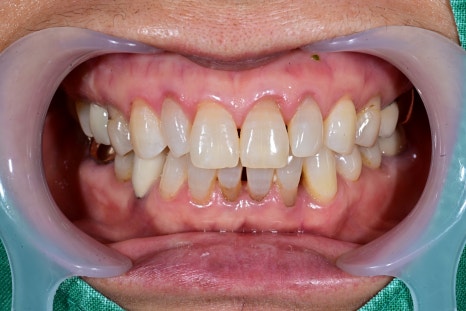

In fact, a female patient in her 60s who visited Seoul Oue Dental Hospital

came in because the upper right molar area kept becoming loose.

Previous image

Next image

The examination showed that the jawbone had weakened significantly,

making it difficult to preserve the natural tooth,

and it was decided to restore function through implants.

After the final prosthetic was placed,

the patient said it felt “like my original tooth.”